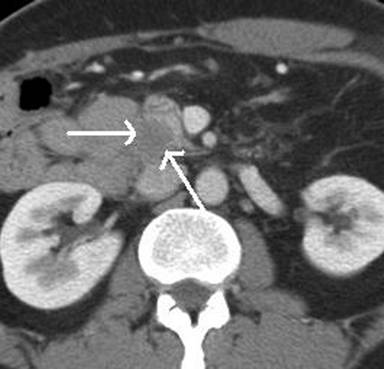

Pancreas-preserving total duodenectomy was performed in 2009, with fashioning of a neoduodenum from jejunum. Histopathological examination of the resected specimen revealed a focus of adenocarcinoma. Post-operative baseline computerised tomography (CT) revealed no peripancreatic abnormality (Figure 1). Follow-up CT after one year demonstrated a 2 cm hypodense mass between the neoduodenum and the uncinate process (Figure 2), although he remained clinically well. Following further discussion at the multidisciplinary team meeting, it was decided that EUS-guided biopsy (EUS-FNA) should be performed.

Figure 2. Routine one-year follow up CT at the same level demonstrates a new 2 cm hypodense mass (white arrows) displacing the uncinate process anteriorly. |